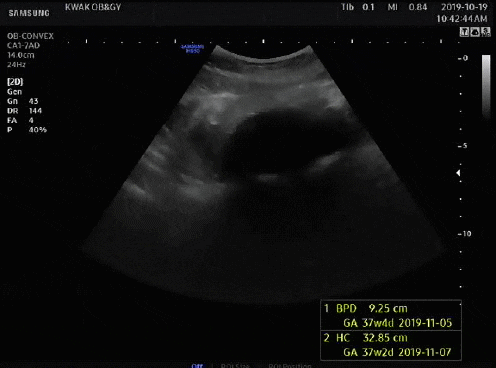

지금은 36주부터 출산까지 매주 목요일 병원에 가서 NST를 통해 태아의 움직임과 심박수, 자궁수축을 기록해 태아가 잘 있는지 확인하고 있다.

산전검사 자궁수축이 없는 상태에서 태아의 움직임에 따른 태아심박동의 증가를 관찰하여 태아의 건강상태를 평가하는 검사. (정의) 분만 전 태아의 건강을 비침습적으로 평가하는 데 사용되는 검사입니다. 이 검사의 정상 결과는 태아의 건강을 반영하는 것으로 해석됩니다. 중추 신경계가 정상적으로 발달한 건강한 태아는 태아 운동의 90% 이상에서 태아 심박수가 증가합니다. 태아 검사가 정상이면 태아가 괜찮다고 안심할 수 있습니다. www.m.terms.naver.com

엄마가 음식(특히 단것)을 먹으면 움직임을 측정하기 쉽다고 한다. 기계 도면으로 인해 태아는 아침보다 밤에 더 활동적이어서 검사 중에는 움직임을 많이 잡지 못했으나 여전히 정상 범위 내이며 심박수는 130~130 사이에서 관찰하기 쉽습니다. 170. 1차 검사에서 큰 1개, 작은 3~4개 적발돼 정상이었다. 분만 시 자궁수축이 더 잦아진다고 하는데, 분만 브이로그를 보면 분만 당일 강도가 100을 넘는 게 규칙적이다. B-초음파는 양수의 양과 태아의 위치를 확인하기 위해 매주 할 수 있는 것 같고, 양막의 크기는 큰 것 하나, 정상인 것 하나 총 두 번 측정했다. 응! ! ! ! ! ! ! ! ! 긴 의료 설명, 의사가 마지막에 추가했습니다. 정상, 괜찮습니다. 동양인 엄마의 체형(골반), 아기의 머리둘레, 회음부절개에 대해 물어봤습니다. 미국에서는 관장, 제모, 외음절개술을 시행하지 않는 것으로 알려져 있지만 외음절개술이라면 의학적으로 필요하거나 필요하다고 합니다. 머리둘레 걱정했는데 제왕절개까지 고려하기엔 역부족이었고(조건은 자연분만일 수 없음: 아기의 몸무게는 5kg임), 산도에서 나오면 아기의 머리 모양이 질 입구에 딱 맞으니 걱정하지 마세요. 걱정되는 저를 안심시키기 위해 의사선생님께서 의료진이 최선을 다해 도와드리겠다고 말씀해주셨습니다. 저도 오늘 B초음파를 하는 이유가 궁금했는데 그게 아니라서 모른다고 하더군요. 이유. 미국의 대답. 오늘 만난 의사는 최근 이상한 변호사 Wu Yingyu를 보는 것을 즐겼다고 말했습니다. 그래서 치료받는 내내 웃음을 참을 수 없었습니다. 덕분에 불안한 마음이 많이 진정되었어요~ 산모가방 싸기 파워J형 K형 산모가방 미국 병원에 있어요~ 정상분만 1박2일만에 퇴원하고 3일만에 그리고 제왕절개 2박.. 한국처럼 큰소리로 산부인과 가방을 싸갈 필요도 없고, 준비물은 다 구비되어 있다고 해서 퇴원할 때 아기옷, 잠옷, 기타 등등 챙겨가셔야 합니다. 산모에게 안정적인 담요를 제공할 수 있는 것. 필요없으시면 다시 가져가시면 됩니다. 필요하지만 그것 없이는 살 수 없습니다. 그래서 제가 챙겨가는 것은 여권, 보험증, 속옷(수유브라), 수면양말, 겉옷, 면속옷, 수유패드, 수유패드, 가슴확대키트, 유축기, 유두보호대, 손목싸개, 회음부패드, 비데, 영양제, 임부복(산모안전속옷), 생리대(1박), 세면도구, 구강청결제, 립밤, 헤어밴드, 기초화장품, 스트레치마크크림, 실내슬리퍼, 휴대폰충전기, 보조배터리, 마스크, 알약, 간식 /다과, 카시트, 포대기, 핸드백, 포장지(담요), 거즈손수건, 젖병, 겉옷(바디슈트), 아기모자, 물티슈, 비타민D, 유산균* 출생신고가 필요하여 퇴원 전 아기의 이름을 정했습니다. 아기의 이름은 최종 후보 2명까지 고려 중이지만, 생년월일과 시간을 보고 최종 결정하게 된다. 산부인과/산부인과/학과 전문용어 외우기 언어차이 극복 미국에서 출산이라는 번거로운 일을 앞두고 가장 걱정되는 것이 언어와 문화차이인 것 같아요. 언어차이는 있지만 통역사들이 있긴 한데… 통역사들의 질이 별로 좋지 않고, 케이블에 제약이 있어서 아기가 생기면 통역사를 안 쓸 생각입니다. 생명이 위급한 상황에서 자신을 보호하기 위해 관련 용어를 숙지합니다. 조산전 산부인과 산부인과 GYN 산부인과 소아과 소아과 둔위전위 태반 미숙아/미숙아 양수 양막 양막 양막 SROM(자발성 막 파열) 파열, 양막 파열 태반 태반 임신 전 당뇨 거림메스꺼움 데데이트, EDD(예상분만일), 자연분만, 자연분만, 제왕절개, 제왕절개, 태아태아, 지진마사지, 막스윕입원, 병원 둘라 / 자간전증이 있는 임산부(증상: 단백뇨, 두통, 부종 등) 저혈압, 저혈압(체외수정) 비스트레스 검사(NST) 경험, 임산부가 편안하게 눕힌 후 20분 동안 산모의 복벽에 모니터를 설치하여 태아 심박수 모니터링 파악 태아의 건강 상태 분만(시간), 분만(과정) 분만, 분만 분만 수축 분만 수축 실제 분만 수축은 점액 마개를 드러내고, 혈액은 자궁 수축을 보여줍니다. 미국 선택, 필요한 경우 37-8주부터 시작) 자궁경부 검사, 내부 검사 내가 확장되고 있는지 확인할 수 있습니까? 확장(자궁문이 열림을 나타냄/0-10cm) 무통 경막외 마취 주사 태아 운동 분만 유도, 분만 유도 흑선 외음절개 회음부(또는 질) 열상(또는 열상) 1도 열상: 1도- 2도 열상(피부 및 피하 조직에 한하며 심한 출혈을 일으킬 수 있는 요도주위 열상 포함) – 2도 열상: 2도 열상(질 괄약근의 근막 및 근육층에 나타나며 항문 괄약근은 영향을 받지 않음) – 3도 열상 열상: 3도 열상(항문 괄약근 및 직장질 횡격막에 영향을 미침) -4도 열상: 4도 열상 상부(항문 및 직장 점막에 영양 공급, 이때 완전히 치료하지 않으면 직장질 누공으로 이어질 수 있음) 관장 산도 탯줄, 탯줄 겸자 산파, 겸자 조산 진공 펌핑 회전(알코올) 버전 정맥주사, 정맥주사 담당의사가 담당의사 대기 중 의사가 퇴원하여 신생아 집중치료실 NICU가 저림 및 출혈 산후출혈 산후 통증 초유, 분유 전 황색 산후 2~3일 묽은 분비물 모유 수유 중 태변 황달/황달 모유 수유 금이 간 유두 황달, 수유 중 또는 수유 사이에 지속적인 유두 통증, 유방 충혈, 분만 후 유방 통증 또는 전신 모유 수유 염증, 유방 통증 유륜 건선 Fluff Lanugo Sitz B형 간염 연고 가임력 산모 피임약 GBS Bacterial Check (37주 + 5회) Group B Streptococcus Bacterial Check 임산부의 질이나 직장에 상주하는 GBS(Streptococcus B)는 신생아 패혈증 및 수막염의 주요 원인 . 신생아가 GBS에 감염되면 일부는 사망하고 생존하더라도 합병증이 발생해 후유증을 동반할 수 있다. GBS는 임산부의 생식기나 위장관에 특별한 증상이 없지만 자궁이나 출산 중 감염을 일으킬 수 있습니다. 따라서 35~37일 말에 GBS 검사에서 양성 반응을 얻으면 분만 내내 항생제나 조치를 취해야 한다. 흔한 세균이고 산모 4-5명 중 1명이 양성 반응을 보여서 크게 걱정하지는 않지만 음성 반응이 나오기를 바라고 있습니다. 개별 포장된 의료용 면봉으로 질입구 -> 직장입구 순으로 5~7회 이상 닦은 후 면봉봉을 절취선에 따라 부러뜨린 후 용기에 삽입합니다. 1~2분 정도 소요되며 매우 간단합니다. 코로나 자가진단키트 느낌. 결과는 며칠 이내에 앱을 통해 받을 수 있습니다. 지난달 메디신볼 운동으로 골반이 활짝 열렸으니 계속 해보세요! 도움을 받을 수 없는 상황이기 때문입니다. 그래서 37주차에 들어가면서 하루에 30분씩 런닝머신 + 엑서사이즈 볼을 하고 있습니다. 내 골반이 부드러워졌으면 좋겠다. . . 집에서 운동을 많이 하지는 않는데 이 영상은 15분짜리입니다. 시간가는 줄 모르고 그냥 따라갔어요. 남편과 소중한 시간을 보내세요. 한동안 우리 집에서 조용한 시간은 없을 텐데(feat. 칼리 날씨) 이제 부모님 오실 날도 일주일 앞으로 다가왔습니다. 그들은 친밀한 시간을 보내고 있습니다. 육아에 직격탄을 맞으면 임시 연애는 어려울 수 있다. 결혼 후 3년간의 격렬한 놀이, 술, 여행. 그들은 신혼부부로서 할 수 있는 모든 일에 자부심을 가지고 있습니다. 슬프다, 이상하다고 생각한다. 캘리포니아의 날씨는 요즘 늦봄(15~20도) 같아서 공원에 가서 샌드위치+커피를 먹기도 좋고, 교외를 드라이브하며 맛집을 찾아 다니기도 좋고… 마지막인 것 같아서 더 재밌어요 ㅎㅎ 밖에 나가야 할 정도로 먼 길을 갈 수는 없었지만, 가까이 있다는 소소한 행복이 출산의 설렘을 달랬습니다. 부모님이 오신 후에도 우리 가족은 적어도 일주일 동안 외식을 하고 당일치기 여행을 할 수 있었습니다. 원하다… !